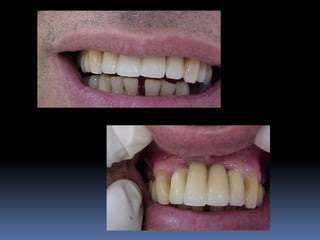

Guia estético

•Simulação da prótese a ser confeccionada,

informando durante planejamento as

possibilidades protéticas ao paciente

(consentimento e colaboração)

•Com o auxílio de fotografias dão noção exata

de como ficará a prótese

•Suporte de lábio superior visualizado com

enceramento

•Necessidade de cirurgias reconstrutivas tais

como enxertos ósseos, gengivais e distrações

osteogênicas

•Alinhamento, desgastes e plano articular e

oclusal em relação ao rebordo alveolar